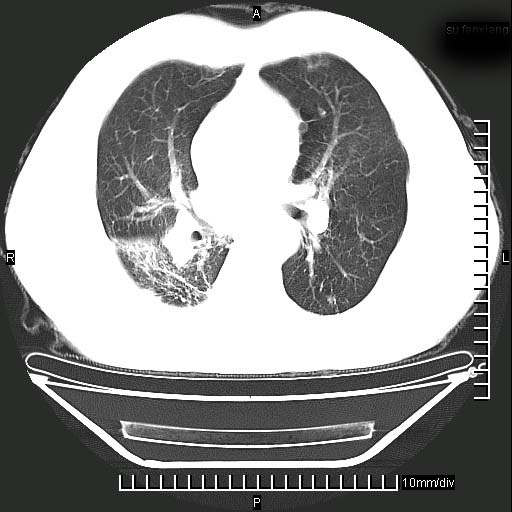

标题: CT24043:胸部增强:男性,60岁

既往肺结核,近10几天,咳嗽,咳痰,右侧胸痛,疼痛较明显,右上肺斑块考虑结核灶胸膜粘连,增强,可惜动脉期没有定好,未见强化,可延迟4分后又见较明显强化,中心见低密度影,如果说结核是边缘强化,可这个灶强化的面积挺大的,让人很挠头。

1)两肺继发性肺结核。2)右侧胸膜增厚+少量胸腔积液。